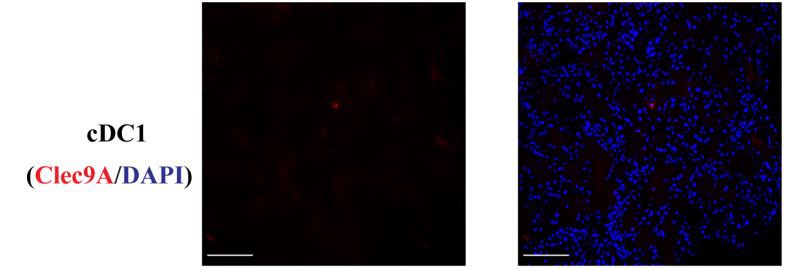

FIGURE 1 | Normal kidney cDC1 (Type 1 dendritic cells), cDC2, and CD8+ T cells.

DCs (Dendritic Cells) were rarely present in normal kidneys and cDC2 numbers were approximately 7 times the number of cDC1 (Type 1 dendritic cells). (Bar = 100 mm).

Number and Location of DCs (Dendritic Cells) in Control and Disease. cDCls were rarely present in normal kidneys(Figure 1) and cDC2 numbers were approximately 7 times the number of cDC1 (Type 1 dendritic cells).The number of cDC1 (Type 1 dendritic cells) increased significantly in ATN and proliferative GN(Figure 2A), while their number remained unchanged compared to control in AIN, membranous nephropathy, MCD, and diabetic nephropathy (Supplementary Figure 3). The number of cDC2 also increased significantly in ATN and proliferative GN(Figure 2B). There was a reduction in the cDC2 (Type 2 dendritic cells)/cDC1 (Type 1 dendritic cells) ratio indicating cDCl (Type 1 dendritic cells) increased proportionally more than cDC2 (Figure 2C).